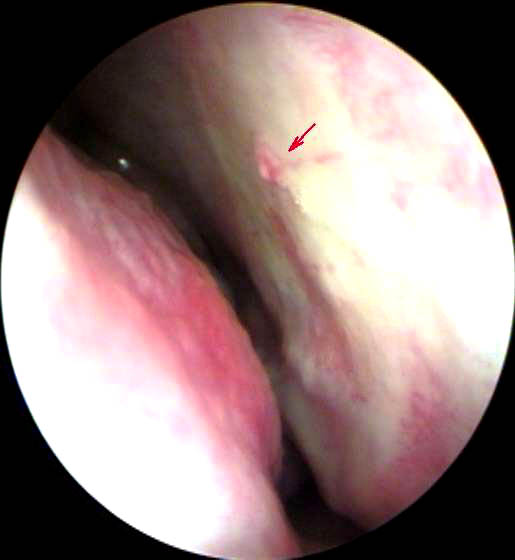

JFC Disfonía cronica por vergetures.